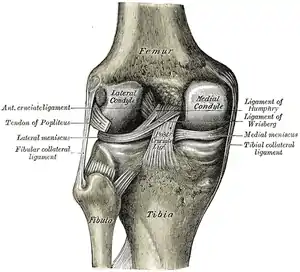

Diagram of the knee

The PCL is located within the knee joint where it stabilizes the articulating bones, particularly the femur and the tibia, during movement. It originates from the lateral edge of the medial femoral condyle and the roof of the intercondyle notch[2] then stretches, at a posterior and lateral angle, toward the posterior of the tibia just below its articular surface.[3][4][5][6]

The PCL, ACL, MCL, and LCL are the four main ligaments of the knee in primates.